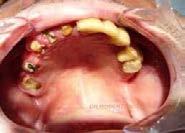

El paciente que es candidato a recibir radioterapia de cabeza y cuello debe ser sometido a una exploración minuciosa de la cavidad oral, a fin de tener un diagnóstico preciso de cada parte de su boca y tratar cualquier patología que se descubra.

Imagen 8. Osteorradionecrosis de los maxilares Imagen 7. Osteorradionecrosis de los maxilares.

La etapa previa a la radioterapia es el momento ideal para poder determinar qué dientes pueden ser restaurados y cuáles no, con la finalidad de realizar las exodoncias necesarias así como cirugía oral, con al menos 3 semanas de anticipación para lograr una adecuada cicatrización. Se deben realizar los tratamientos odontológicos que requiera el paciente, tales como, eliminación de caries, eliminación de sarro dental y posibles bolsas periodontales, eliminar cualquier prótesis, dentadura o borde filoso que pueda ocasionar irritaciones o lesiones en la mucosa. Es muy importante enfatizarle al paciente que debe cumplir con una higiene oral escrupulosa, así como acudir a revisiones frecuentes para aplicación tópica de flúor.

La situación cambia radicalmente en las etapas de irradiación y postradiación. Como ya se ha mencionado, el tejido óseo irradiado es “3 H”, hipocelular, hipovascular e hipóxico, por lo que al no tener capacidad de regeneración, las exodoncias y cualquier otro procedimiento que implique trauma a estos tejidos, deben evitarse hasta por un periodo de 10 años posteriores a la radioterapia (Imagen 7 y 8).